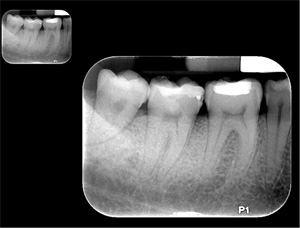

Un conjunto de radiografías tipo bitewing usualmente consiste de cuatro radiografías que se colocan cerca de los molares. Se les conoce como bitewing debido a que se muerde sobre una aleta de cinta o cartón para sujetarlas en su sitio. Las radiografías de tipo bitewing reflejan la corona de los dientes molares y premolares y la altura del hueso entre los dientes, ayudando en el diagnóstico de caries y enfermedades periodontales. Las radiografías tipo bitewing se recomiendan en intervalos de un año. Su dentista puede recomendar tomarlas con más o menor frecuencia, basándose en su salud oral.